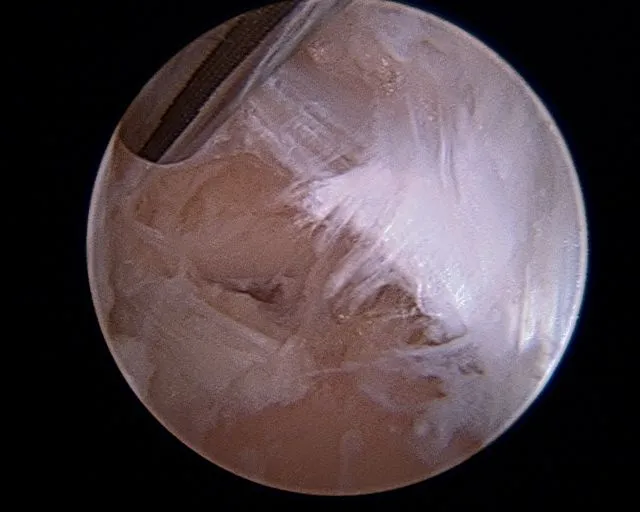

Cleaned out middle facet

Scar tissue and fibrous band in the subtalar joint